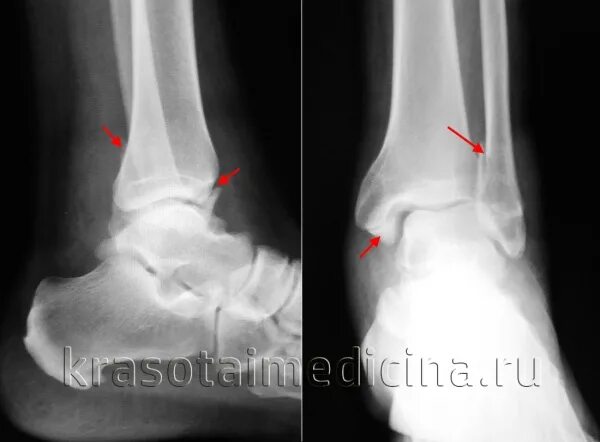

Разрыв связок голеностопного сустава мкб 10